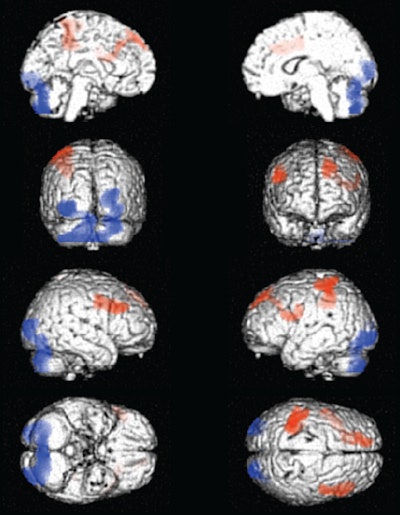

Ferrando and colleagues found that active users generally showed hypoperfusion, or decreased blood flow, in the mesial frontal, anterior cingulate, medial orbitofrontal, thalamic, and midbrain regions. Abstinent subjects showed hypoperfusion in the right temporal, medial orbitofrontal, midbrain, and cerebellar regions.

Active users also generally showed cerebellar hyperactivity, whereas those abstaining from cocaine use had left frontoparietal hyperactivity.

There was an apparent reversal of brain dysfunction in the prefrontal cortex of now-abstinent cocaine users, according to the researchers. Compared with active users, the abstainers showed increased perfusion in the dorsolateral frontal and left parietal areas of the brain, but also decreased perfusion in the posterior occipital cortex and in the cerebellum.

The partial reversal of dysfunction in the abstinent cocaine users "may reflect an improvement in limbic balance, emotional control, and adapted behavior that is seen in abstinence subjects compared to active users," Ferrando and colleagues wrote.

"Improvement of frontal function may place the subjects in a better position to decide what is best for themselves and their future over the immediate reward the drugs can offer," Ferrando said. "In other words, these images show how the brain of the abstinent subject can gradually retrieve the necessary tools to stay away from drugs."